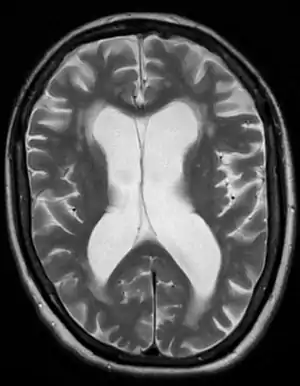

- Normal pressure hydrocephalus (NPH) is a particular form of chronic communicating hydrocephalus, characterized by enlarged cerebral ventricles, with only intermittently elevated cerebrospinal fluid pressure. Characteristic triad of symptoms are; dementia, apraxic gait and urinary incontinence. The diagnosis of NPH can be established only with the help of continuous intraventricular pressure recordings (over 24 hours or even longer), since more often than not instant measurements yield normal pressure values. Dynamic compliance studies may be also helpful. Altered compliance (elasticity) of the ventricular walls, as well as increased viscosity of the cerebrospinal fluid, may play a role in the pathogenesis.

- Hydrocephalus ex vacuo also refers to an enlargement of cerebral ventricles and subarachnoid spaces, and is usually due to brain atrophy (as it occurs in dementias), post-traumatic brain injuries, and even in some psychiatric disorders, such as schizophrenia.[19] As opposed to hydrocephalus, this is a compensatory enlargement of the CSF-spaces in response to brain parenchyma loss; it is not the result of increased CSF pressure.[19]